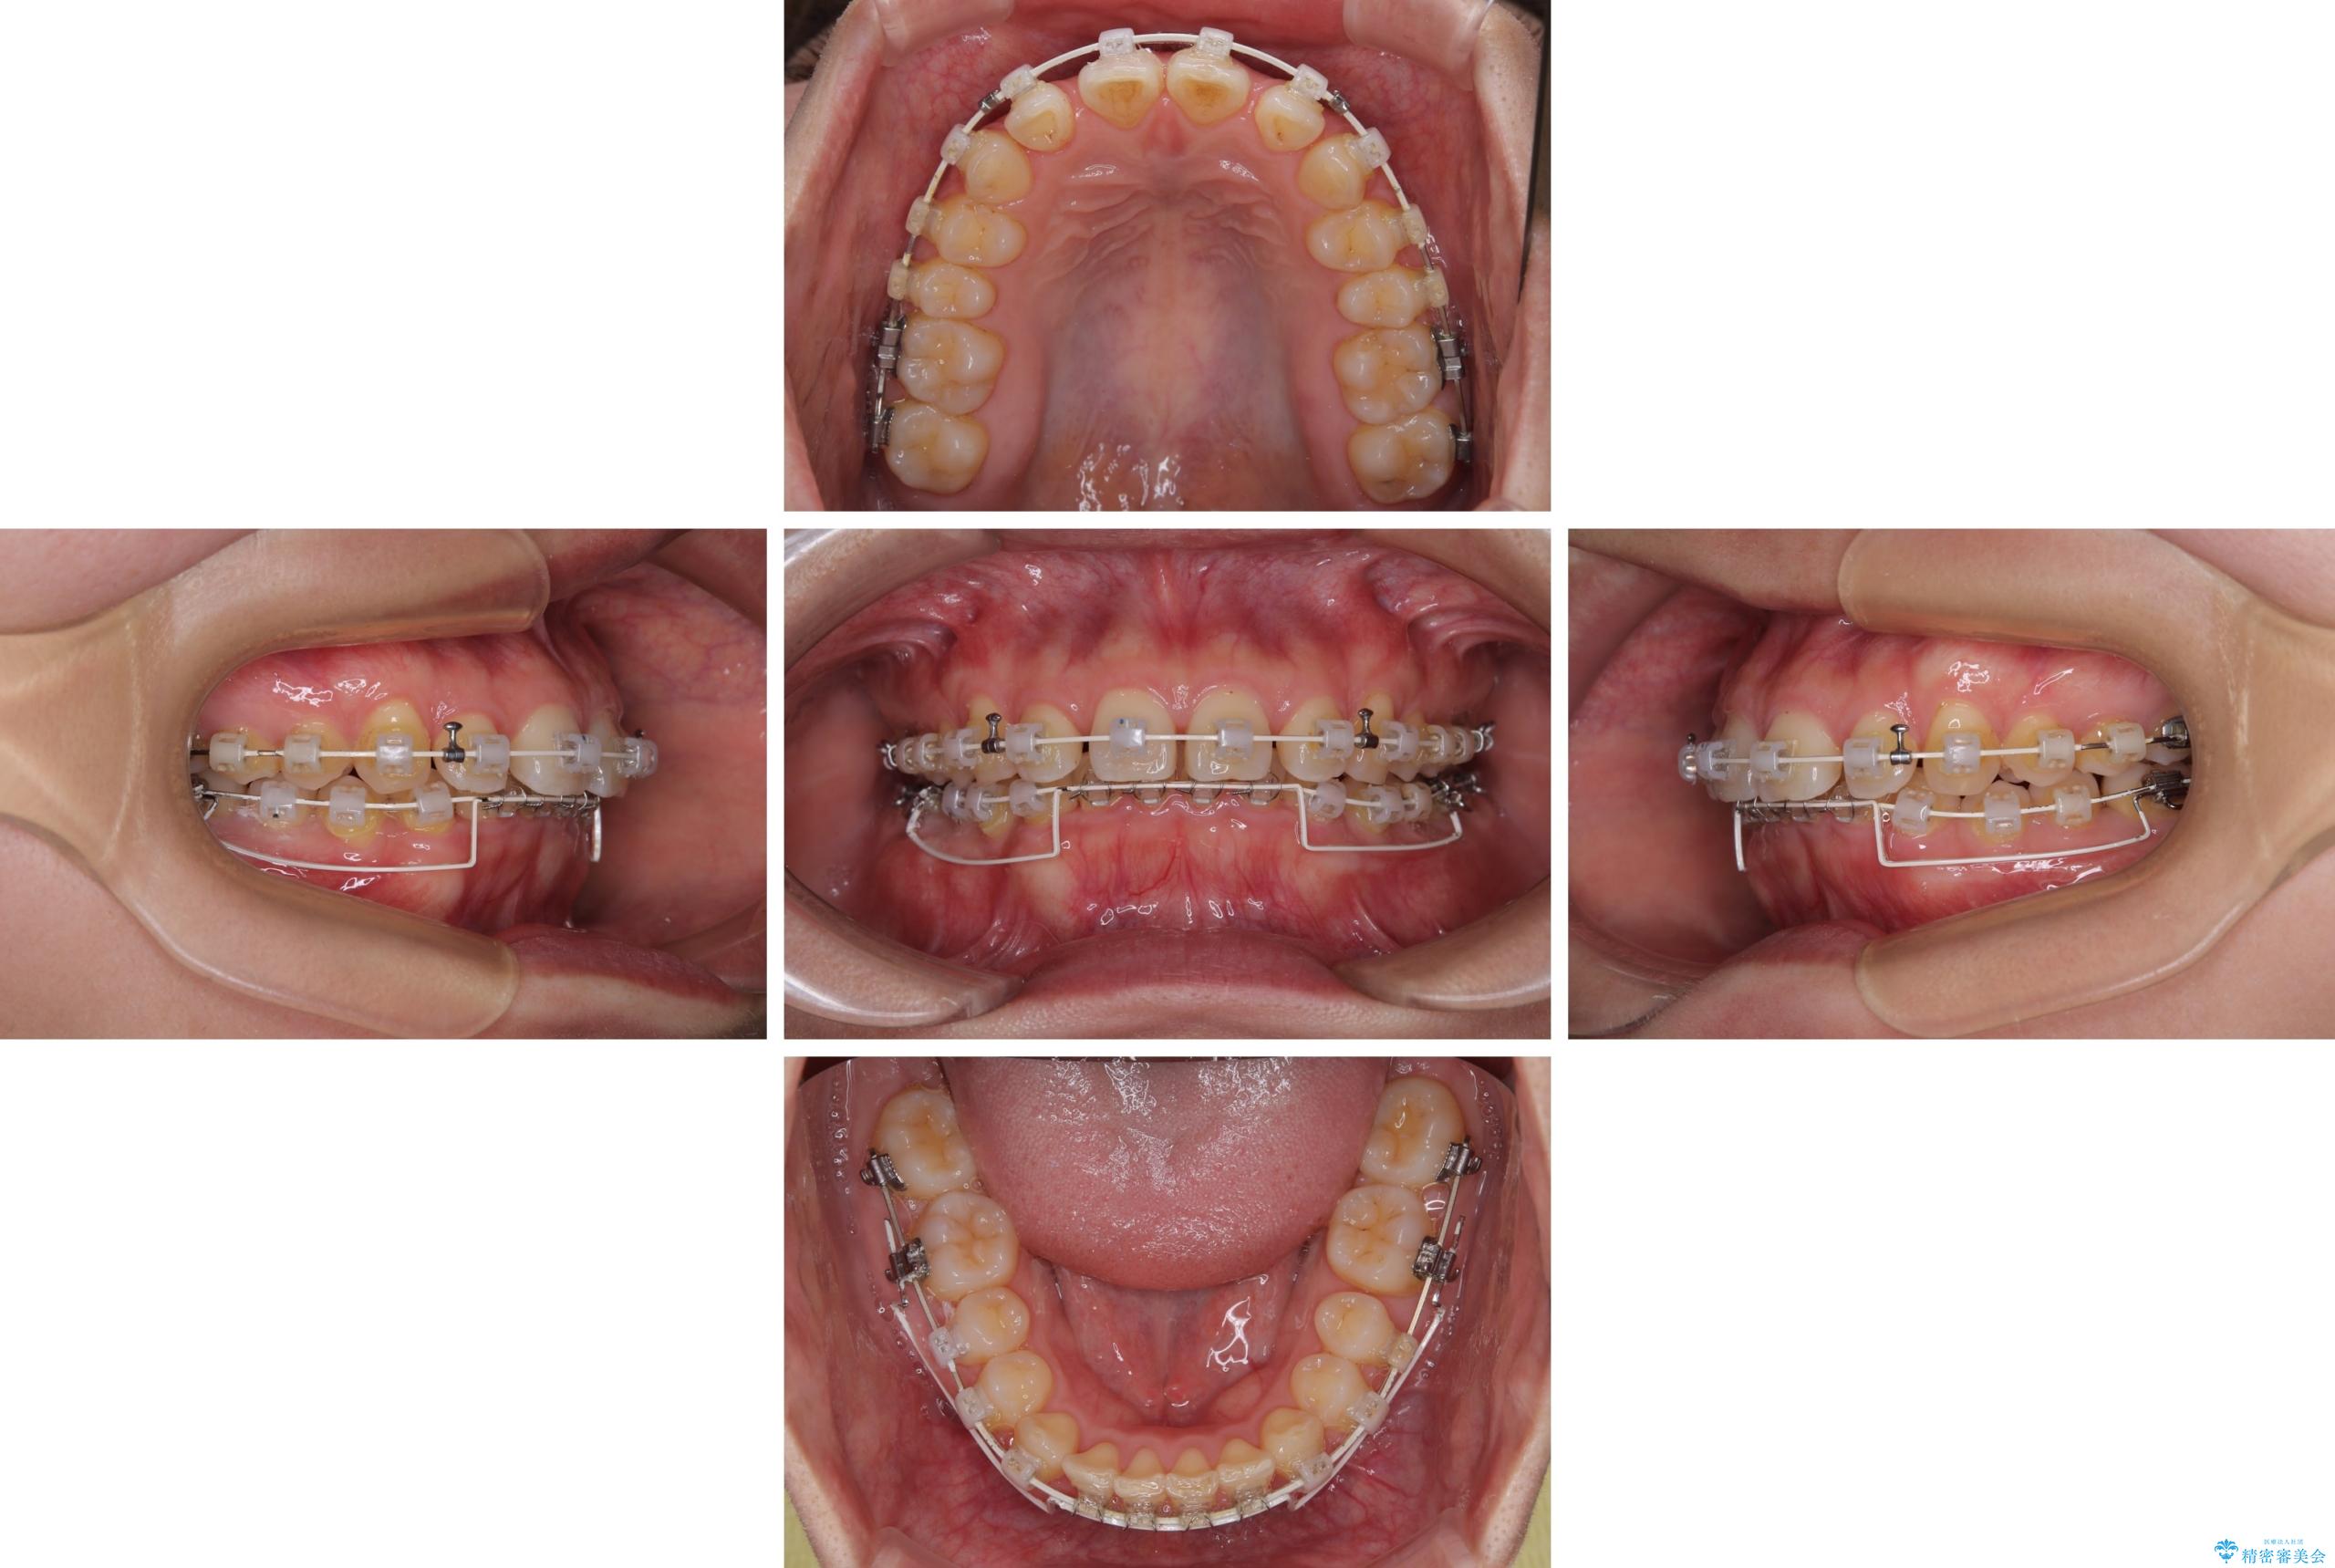

隠れた前歯が気になる ディープバイトのワイヤー矯正治療

- 下顎前歯が完全に隠れてしまっていることを気にして来院された患者様です。

下顎の臼歯が手前に傾斜していることで咬み合わせが深くなってしまい、下顎前歯が見えないほどに上顎前歯が覆い被さっている状態でした。

下顎臼歯を起き上がらせるためにユーティリティーアーチを使用し、一気に深い咬み合わせを改善することができました。